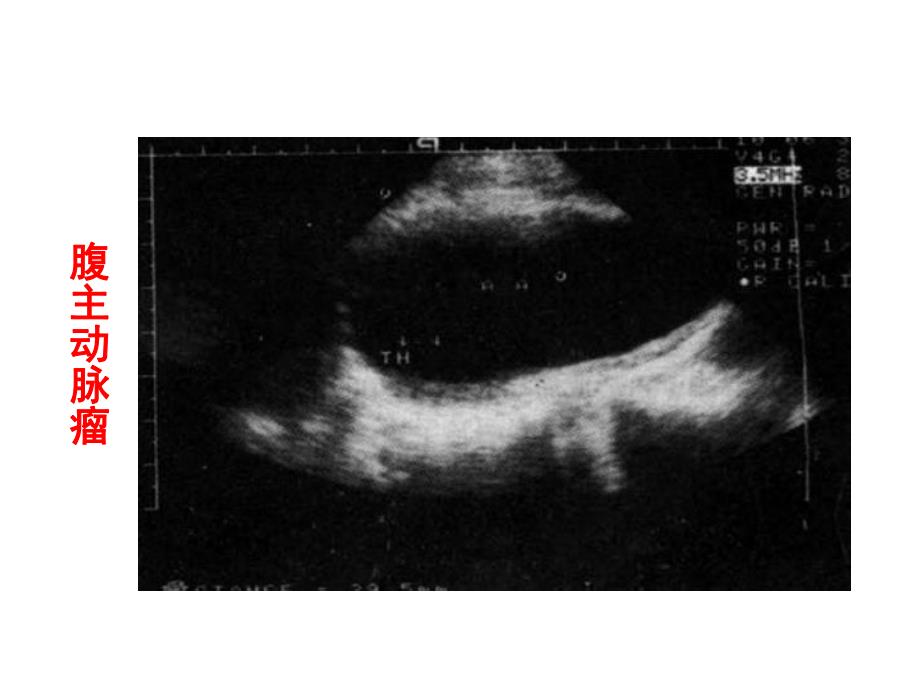

1、超声诊断学超声诊断学超声诊断学超声诊断学腹主动脉瘤腹主动脉瘤 第三节 腹部大血管周围血管超声诊断超声诊断学超声诊断学 腹主动脉瘤腹主动脉瘤超声诊断学超声诊断学真性动脉瘤真性动脉瘤多发性腹主动脉瘤多发性腹主动脉瘤超声诊断学超声诊断学真性动脉瘤真性动脉瘤多发性腹主动脉瘤多发性腹主动脉瘤超声诊断学超声诊断学超声诊断学超声诊断学 二二超声诊断学超声诊断学超声诊断学超声诊断学超声诊断学超声诊断学超声诊断学超声诊断学超声诊断学超声诊断学超声诊断学超声诊断学超声诊断学超声诊断学 超声诊断学超声诊断学 超声诊断学超声诊断学 超声诊断学超声诊断学 腹主动脉主动脉夹层分腹主动脉主动脉夹层分离离超声诊断学超声诊断学